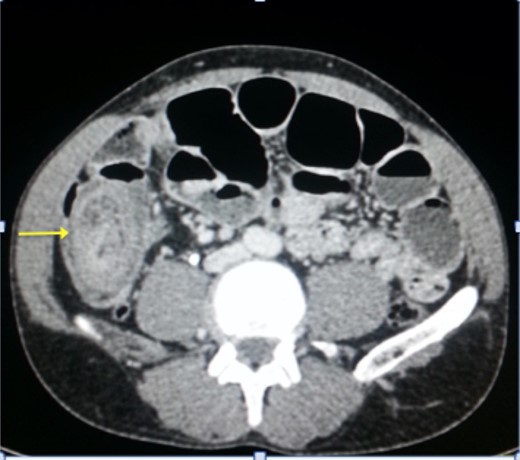

A plain abdominal radiography suggested a bowel obstruction, by showing multiple air-fluid levels. Biological results were the following: hemoglobin: 13,5 g dl−1, hematocrit rate: 42,5%, white blood cell count: 8×103 mm−3, creatinine = 18 mg L−1, serum Na: 139 m Eq L−1, serum K: 3.4 m Eq L−1. The contrast-enhanced CT showed a target mass localized in the right iliac fossa, and was suggestive of ileocecal intussusception without specifying the underlying cause (Fig. 1). While coronal reconstruction showed a « sausage-shaped mass » (Fig. 2). Moreover, there was some lymphadenopathies surrounding the target mass, and a small amount of abdominal effusion.

Coronal reconstruction of abdominal CT showing the ‘sausage sign’ of ileocecal intussusception.

The classic ‘target mass’ picture on CT scan as found in our case, is pathognomonic of intussusception [6]. It consists in a central dense area and a halo of low attenuation being respectively the intussusceptum and the edematous intussuscepiens [7, 8]. In a sagittal view, we found the classical « sausage sign » in our patient. Moreover, CT scan may identify the underlying cause of the intussusception [1]. The common sites of occurrence of this condition are the junction between the movable segments of the intestine and segments that are relatively fixed as in our case.